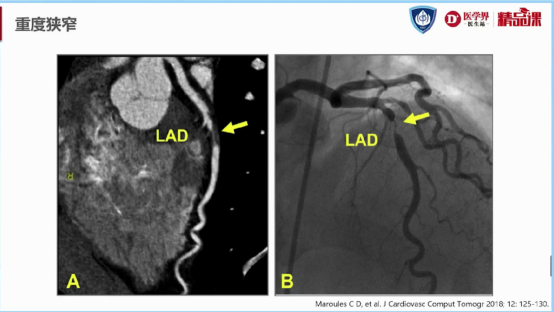

图9:前降支重度狭窄(70-99%)示意图